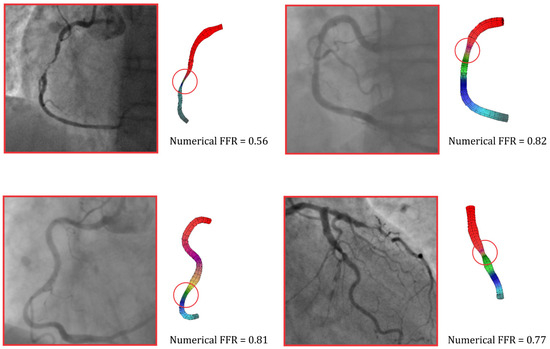

3.3. Numerical Simulation Results

Figure 2 shows the results of four patients after a numerical simulation in the case of a flow rate of 3 mL/s. This flow rate was a standard maximum flow for the measurement of FFR when adenosine was intravenously administrated. A red circle can be seen in Figure 2, which marks the observed stenosis on the artery. As already mentioned, a good agreement between the numerical simulations and the measurements of FFR was obtained, and this was the reason we used numerical results to validate the ML model [25,26].

Figure 2.

Pressure distribution, based on finite element analysis, in the coronary arteries. The FFR value was calculated based on numerical simulations.